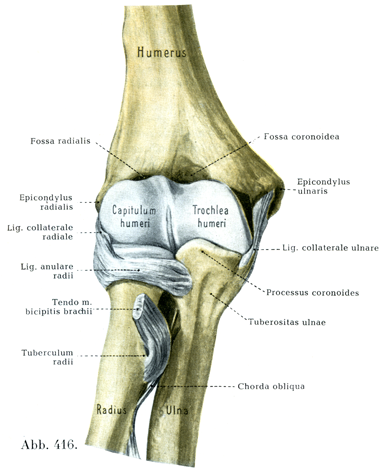

[図416]右の肘関節 屈側(4/5) 関節包はとり去ってある.

肘関節は複合関節であって1つの共通の関節包のなかに腕尺部Pars humeroulnaris,腕橈部Pars humeroradialis,橈尺部Pars radioulnarisという3つの関節をもっている.

関節面は上腕骨では滑車Trobhleaと小頭Capitulum, 尺骨では半月切痕Incisura semilunarisと橈骨切痕Incisura radialis ulnae,橈骨では小頭窩Fovea capituliと関節環状面Circumferentia articularisである.

上腕骨滑車Trochlea humeriは深い溝のついた滑車で,その形は砂時計に似ているといえる.この砂時計状の滑車は円錐形の部分を2つもっていて,そのうち内側の円錐の方が高さ(14mm)においても周(直径14.1mm)においても大きく,外側の円錐の方が小さい(高さ8mm, 直径11.3 mm).しかし両円錐は同一の,斜めに内側やや下方へ走る軸をもっている.さらに滑車全体が前面では後面より2~4mm狭く,滑車の表面の弯曲も,前面では後面より強い.関節軟骨は前面では内側の方がより上方に達しており,後面ではその逆になっている.滑車の溝のところでは関節軟骨は前後両面とも同じ高さにまで達していて,ここでは関節軟骨が滑車の全周のうち中心角280~320°に相当する部分を包んでいる.溝の走行は正確に円形ではなくて,ラセンの一部をなしている.もっともその「ネジの歩み」は個体によって非常にまちまちである.

滑車の内側縁も一種のラセンをえがく(Fick).滑車は外側方では,傾斜した縁と個体的に深さの異なる溝とによって小頭とへだてられている.軟骨は1.5mmの厚さである.軟骨は内側縁で最もうすく(1.2mm),外側縁では2mmにも達する.肘頭窩のすぐ下方では最も薄い.滑車の外側縁では軟骨が疎になり,ほぐされたようになり,あるいはところによっては全く欠けている(Fick)-図416を参照せよ.

上腕骨小頭Capitulum humeriは大体のところ1つの球とみられ,その中心は滑車軸の上にあり,直径は10.5~11mmである.しかし表面の弯曲は方向によって同じでない.軟骨の被いは中央で最も厚く(1~2mm),縁にゆくほど次第にうすくなる.

尺骨の半月切痕Incisura semilunaris ulnaeはだいたいに上腕骨の滑車と一致しているが,Fickは「肘関節がいかなる位置をとっても,半月切痕の全体が上腕骨の滑車に接触す為ということはない」と記している.半月切痕の弯曲は直径10mmの円孤に相当している.上腕骨滑車の溝に対応して,半月切痕には1本の導稜線Führungsleisteがある.関節軟骨は軟骨で被われない横走する溝によって,2つの部分に分けられている(図417, 423, 425).両部分のうち後方のものは肘頭に属し,烏口突尊に属する前方の部分とは弯曲の状態を異にしている.軟骨の厚さは導隆線の両端および橈骨切痕との境界では2mmあるいはそれ以上にも達する.軟骨は内外両縁へと次第に薄くなっている.

[図420] 橈骨 VV橈骨の回旋の鉛直軸, a橈骨の尺骨切痕の中央(H. Meyer)

橈骨小頭窩Fovea capituli radiiはほぼ円形の輪郭をもつ浅いくぼみで,その弯曲は上腕骨小頭の表面と一致している.しかし上腕骨小頭の150°に対して,小頭窩の面はわずかに中心角70~80°に相当するひろがりをもつにすぎない.小頭窩の縁は関節環状面に移行している.しかし内側では小頭窩の縁と関節環状面の上稜とのあいだに,斜めにかどを落したような半月形の場所(斜半月Lunula obliqua, Fick)があって,上腕骨滑車の傾斜した外側縁と関節をなしている.軟骨の厚さは小頭窩の縁ではほとんど2mmに近く,中央では1mmである.